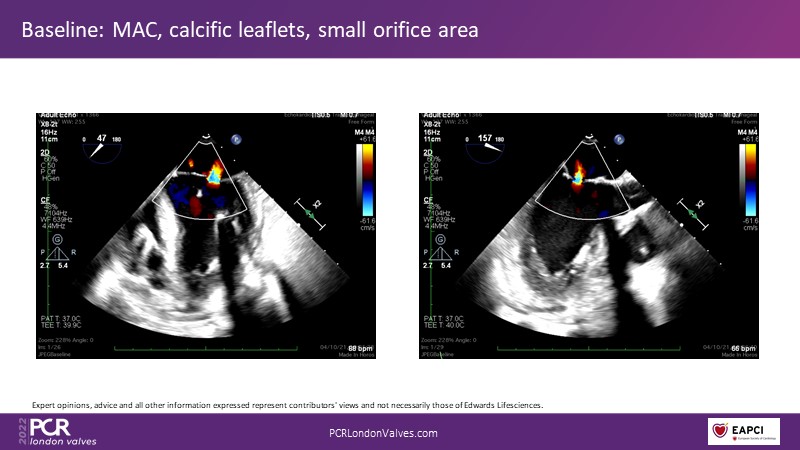

Join this panel of experienced physicians to learn more about the novel PASCAL Precision system and to discuss implant selection and clinical data. Finally, participate in a recorded case demonstrating the use of the PASCAL Precision system for the treatment of mitral regurgitation.

- To discuss the anatomical considerations that define suitable candidates for the treatment of mitral regurgitation with the PASCAL Precision system

- To attend clinical evidence and case-based discussions that will highlight key differentiators of the novel PASCAL Precision system and its clinical impact